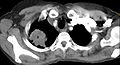

Diagnosis of a Pancoast tumor can be difficult in the early stages to the similarity of its symptoms with other conditions such as arthritis, with shoulder pain being one of the only symptoms that might indicate further imaging for a patient.[14] Though a chest x-ray is a good screening test and might be the first mode of imaging used, they are not easily seen during the early stages of the disease due to their size and location in the chest.[15]

Following the initial imaging, a CT scan or MRI is preferred since both can provide more details and information such as size, lymph node involvement and other areas of invasion, such as vascular involvement.[15][10]